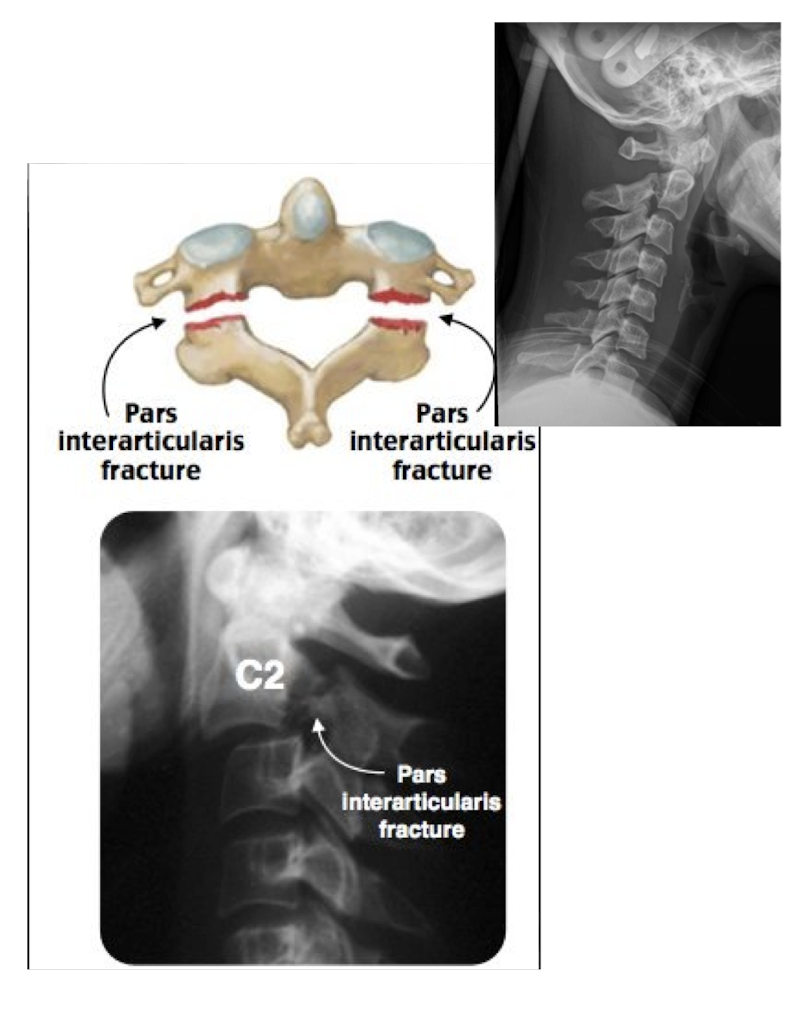

Fracture of C2: Hangman’s Fx

What type of Fx is this?

Bilateral Fx of the pedicles of C2 w dislocation of vertebral body C2 on C3

Fracture of C2: Hangman’s Fx

MOI:

__ for info on the SC

Stable or Unstable Fx

MOI:

Hyper Extension Injury in MVA

MRI

Unstable